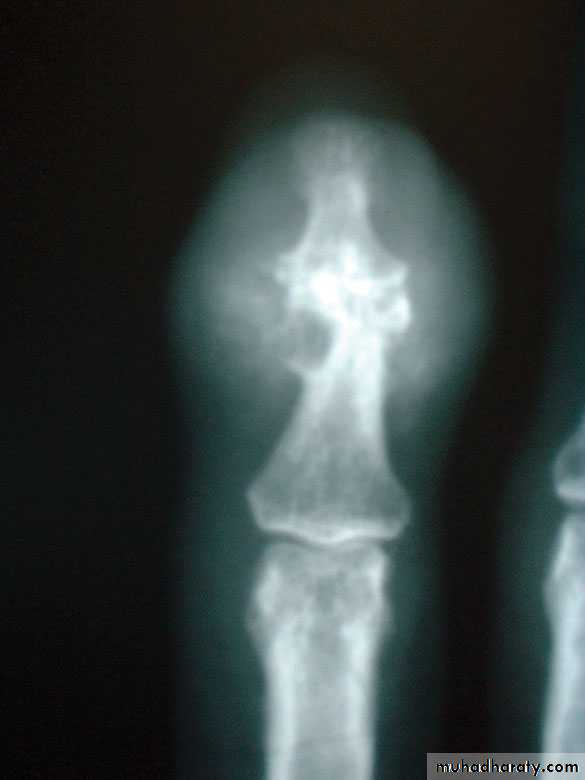

In chronic inflammatory polyarthritis, marginal joint erosions are seen earliest in the small joints of the hands, wrists, and feet in patients with RA.

Chronic gout can also cause erosions with an overhanging edge that typically involve small peripheral joints such as the first MTP joint.